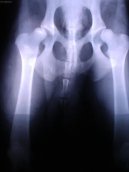

Veterinární zákroky :

Ortopedie - DKK

PSÍ SVĚT: Veterinární poradna

View: 1042x